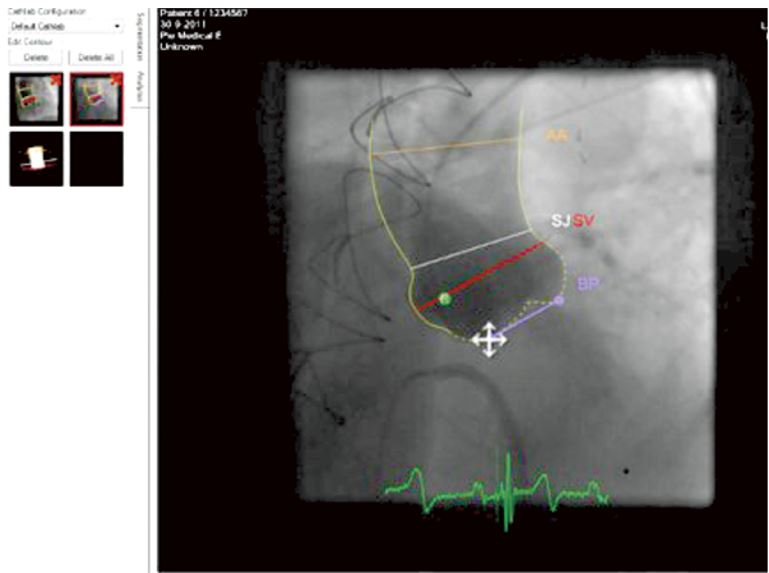

• CAAS A-Valve

CAAS A-Valve може допомогти лікарям під час підготовки або процедури заміни клапана TAVR (або TAVI)

Приклад CAAS S-Valve software

Флюороскопія під час TAVR